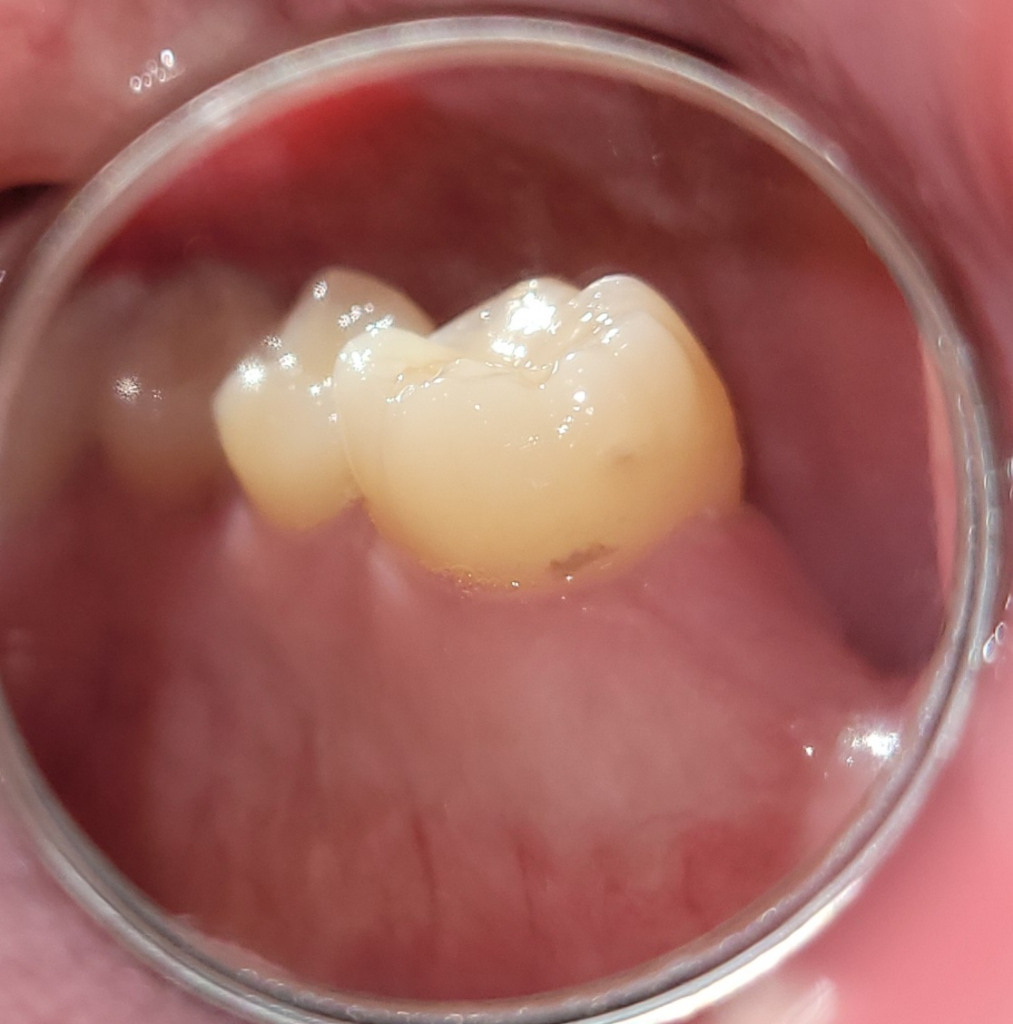

제가 3주전에 어금니를 발치하고 픽스쳐 식립했는데요 사진은 바로 옆 어금니뒷 면 입니다. 두 번째 사진은 발치 전 엑스레이 사진입니다. 마지막은 식립 이후 사진입니다.

이빨 거울 하나 사서 보니까 잇몸 부근에 저런 구멍이 있던데 저거 때문에 시린걸까요?

• 3번 째 사진

치아 발치시에 옆에 있던 치아의 충치 부위가 노출 되면서 시리거나 통증이 발생할 수 있습니다